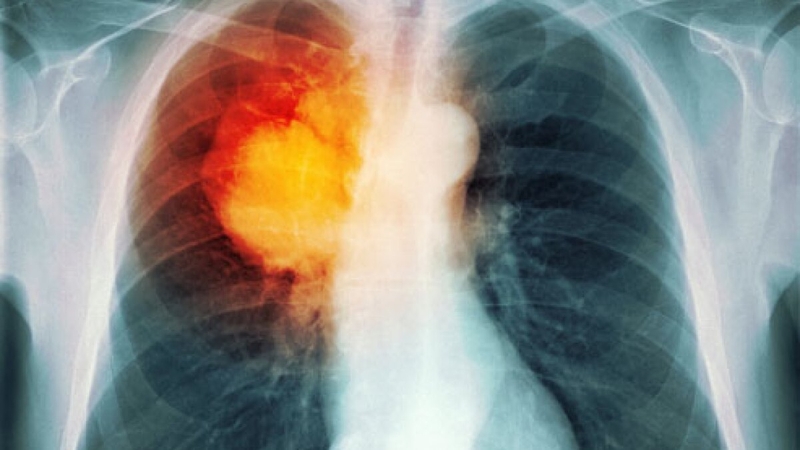

Để kiểm tra, sàng lọc và phát hiện ra những dấu hiệu bất thường của các bệnh lý liên quan đến phổi, X-quang (Xquang) lao phổi được xem là một trong những phương pháp phổ biến hiện nay.

Xquang lao phổi hay còn gọi là X-quang ngực, là một xét nghiệm hình ảnh sử dụng tia X để xem các cấu trúc và cơ quan trong lồng ngực. Nó sử dụng liều lượng bức xạ thấp để chụp ảnh khu vực này. Điều này có thể giúp bác sĩ đánh giá phổi và tim của bạn đang hoạt động tốt như thế nào. Một số vấn đề về tim có thể ảnh hưởng đến phổi. Một số bệnh có thể gây ra những thay đổi trong cấu trúc của tim hoặc phổi.

X-quang lao phổi được chỉ định trong quá trình kiểm tra, sàng lọc các bệnh lý có liên quan đến phổi. Với phương pháp này có thể cho thấy kích thước, hình dạng và vị trí của: Trái tim, Phổi, Phế quản, Động mạch chủ, Động mạch phổi, Xương của lồng ngực.

Để có thể phát hiện và kiểm tra chính xác xem liệu rằng người bệnh có mắc phải bệnh lao phổi hay không, chụp Xquang lao phổi là phương pháp chẩn đoán mang lại tính chính xác cao nhất hiện nay.